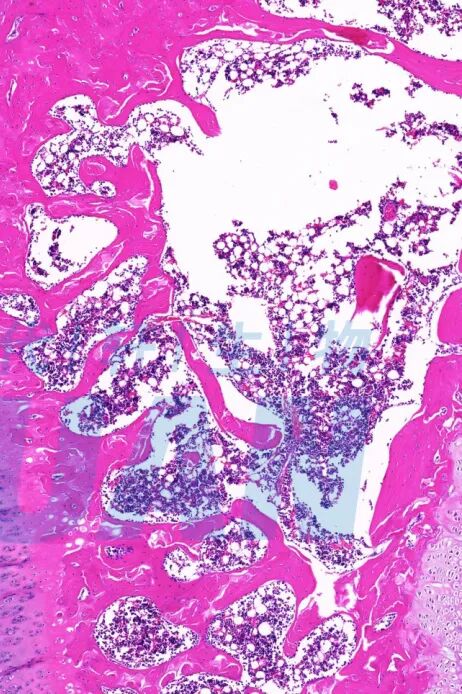

平台提供从常规石蜡/冰冻包埋、切片、HE染色,到超过二十种特殊染色技术的完整服务。无论是常规诊断所需的结缔组织染色(如Masson、天狼星红)、细胞成分显示(如尼氏、吉姆萨),还是针对特定研究的染色需求(如破骨细胞TRAP染色、β-半乳糖苷酶染色),我们均能提供标准化、高质量的结果输出,确保从大体标本到镜下判读的无缝衔接。